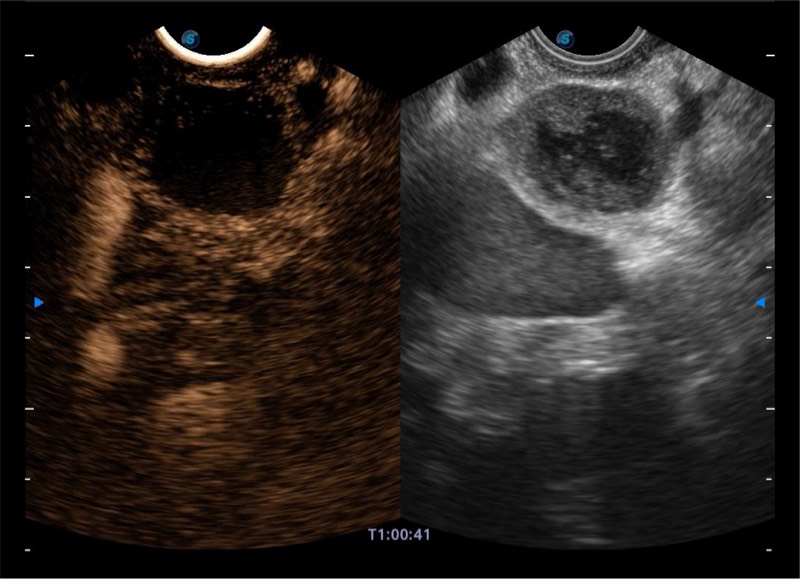

基于二十年的超声技术积累,狗万官方网站提供了最新一代的独立超声主机,在提供高质量图像的同时满足多学科使用。具备常见多普勒技术并提供弹性成像、声学造影等高端影像技术。新一代传感器具有更强的抗干扰能力并减少图像伪影。

4-12MHZ宽频输出